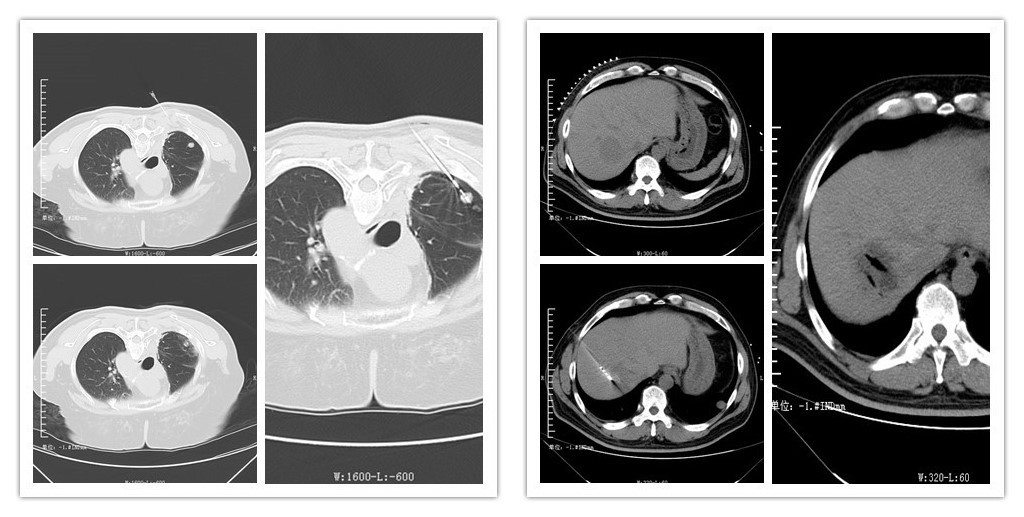

12月21日正值冬至节气,我院肿瘤内一科正如火如荼的为即将开展的肿瘤微波消融治疗做最后准备。当晚17:00—21:30在全科医护人员的共同努力下,我科完成了包括肺脏、肝脏病变共6例肿瘤患者的病灶微波消融治疗,手术顺利,术后患者未出现明显不适。

链接:肿瘤微波消融技术是继我科已开展的肿瘤氩氦刀冷冻治疗、碘125放射性粒子植入技术后的另一种新的肿瘤微创治疗技术。微波消融就是将微波针经皮穿刺到肿瘤内,通过针尖区域释放的微波磁场使肿瘤周围的分子高速旋转并摩擦产热升温,从而使肿瘤组织凝固、脱水坏死,达到治疗肿瘤的目的。一次治疗的时间仅为几分钟,具有定位精准、不开刀、痛苦小、手术时间短、费用低、恢复快、安全性高和疗效确切等优点,是肿瘤综合治疗不可缺少的最佳手段之一。尤其是针对早期不愿手术、手术不能完全切除或切除风险较大的病人、心肺肝功能差等原因不宜手术的病人、转移癌灶多需减瘤、减症的病人等具有良好的适应症。目前广泛应用于肺脏、肝脏、肾脏、肾上腺等实质脏器的原发、转移病灶的治疗。